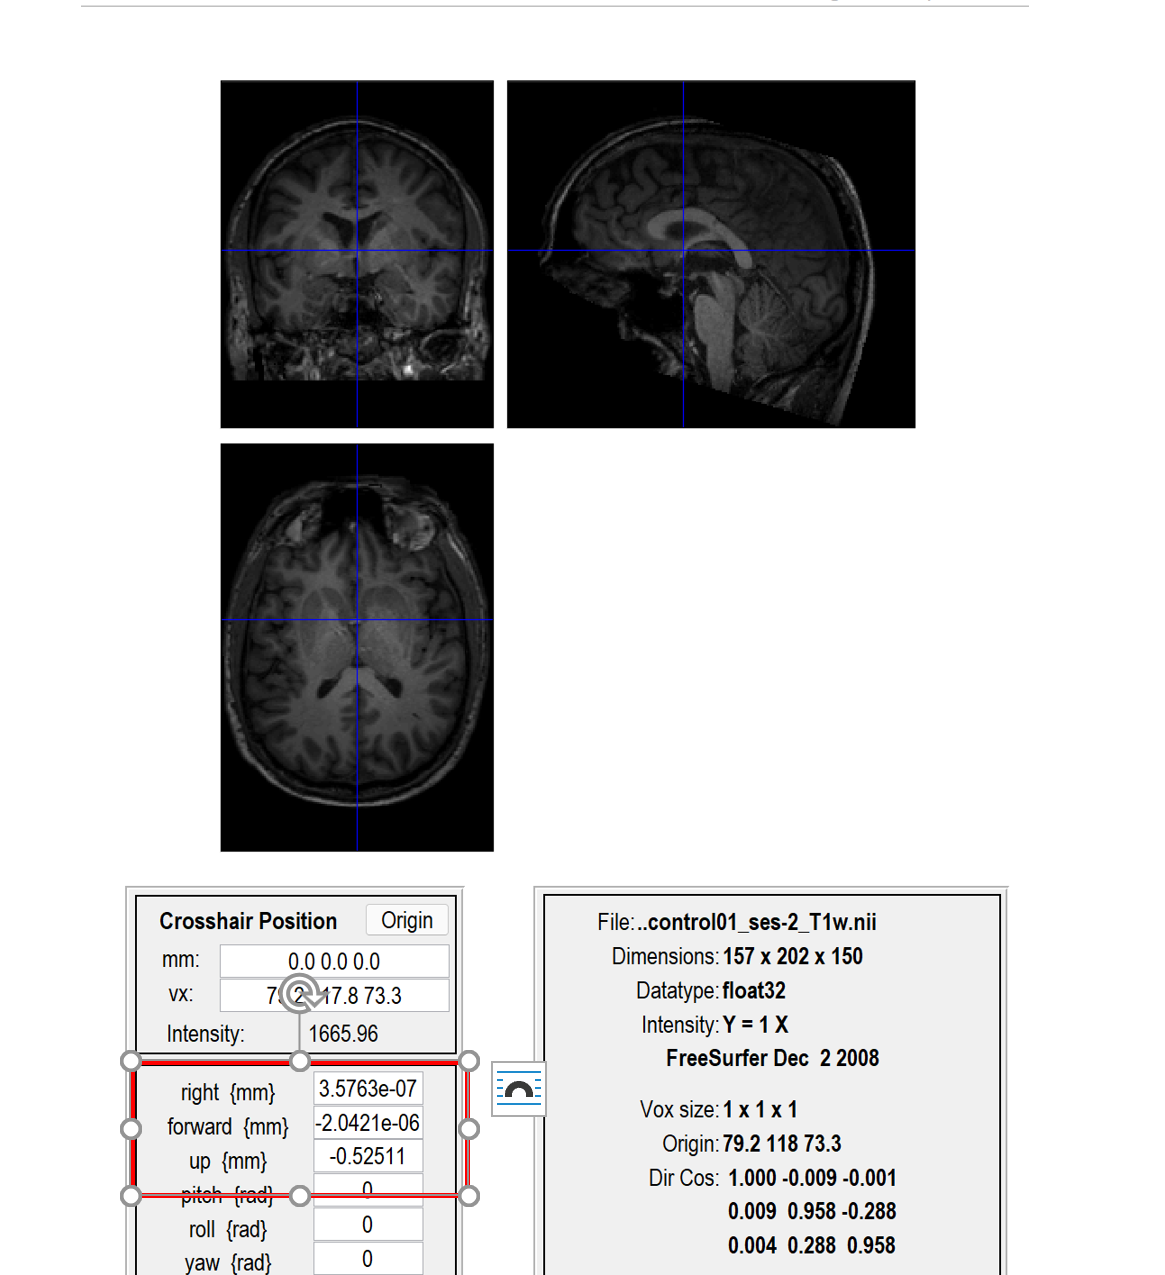

一个这样的页面,我们可以看到一个蓝色的十字线,这个线的交叉点就是我们要调整的地方,手动将交叉点放在大概下图这个位置(就是前联合的位置),前联合的位置怎么确定可以去查一下,网上有很多教程。我的理解就是大概在下图这个红色的圆里。点一下set origin之后就会出现坐标位置。然后一定要点击一下Reorient,才算是调整成功了。在这里插入图片描述在这里插入图片描述

还有就是如果发现自己的数据里的大脑比较歪的话,也可以通过下面的几个pitch roll yaw调一下。我调的时候发现必须0.1,0.2(正负多试几次就知道了)这样的微调,不然变化会很大。